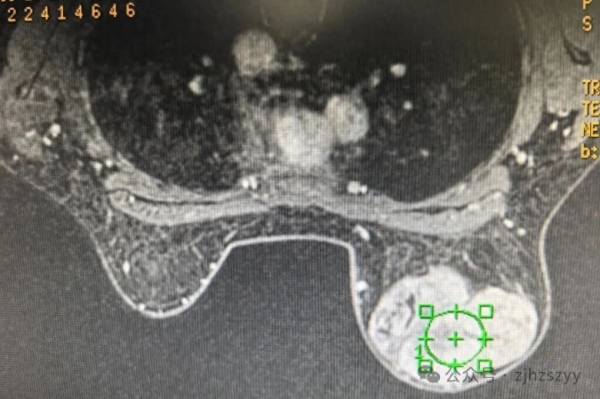

手术图片,请谨慎点开!

叶状肿瘤是一种生长较快的乳腺肿瘤,因其在显微镜下呈现如树叶脉络般的分叶状结构而得名。